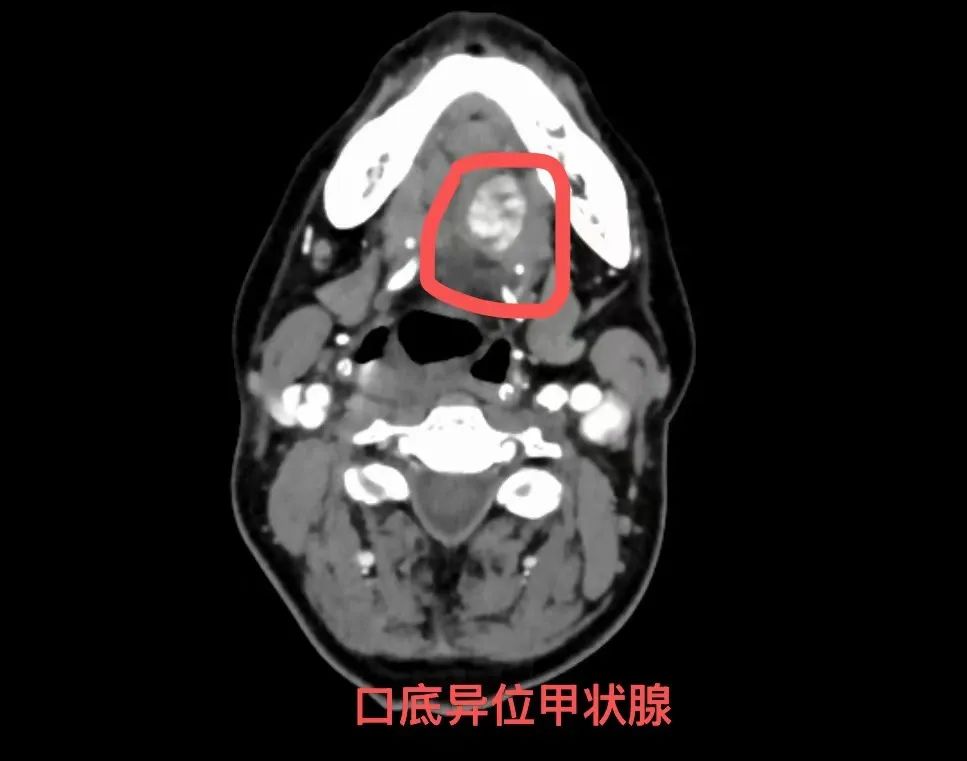

头颈部ETG根据其位置不同,可分为内侧异位、外侧异位和混合异位。内侧异位包括舌甲状腺,舌骨上、舌骨下和胸内甲状腺;外侧异位分为颈静脉旁、颈动脉旁和下颌下甲状腺;混合异位罕见,是指甲状腺实质在颈部多个部位发现,包括甲状腺前肌、颈静脉旁区域,但未累及淋巴结。ETG主要发生在胸部,纵隔多见,同时存在于两个部位的ETG罕见,也有ETG发现于其他部位,如气管、胆囊、肺、心脏、肾脏、胰腺、阑尾及卵巢等。ETG与原位甲状腺具有相同的病理生理,导致原位甲状腺的任何病变也可能累及ETG,包括囊肿、结节性甲状腺肿和甲状腺癌。